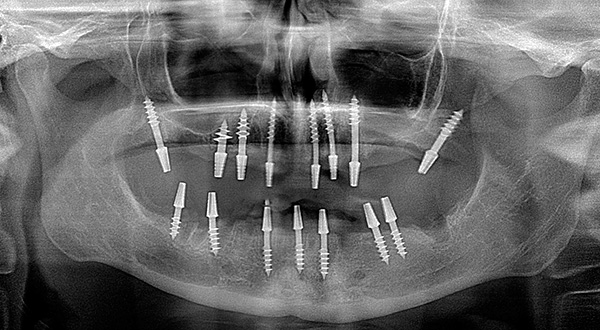

Entre as tecnologias de carregamento imediato, vários protocolos principais podem ser distinguidos: próteses em quatro implantes (all-on-4 - patenteados pela Nobel), em seis implantes (all-on-6) e o próprio método basal.

Em todos os casos, são utilizados implantes instalados precisamente nas camadas profundas do tecido ósseo (existem muitos modelos e variedades desses implantes). Eles estão ligados não apenas na zona alveolar, mas também na seção basal, a membrana cortical do osso. E com atrofia aguda, os ossos e contrafortes zigomáticos (linhas de força) do crânio também são usados. O grau de fixação de tais implantes é várias vezes maior e atinge 100 Newtons versus implantes clássicos, com um índice de 30 a 45 Newtons.